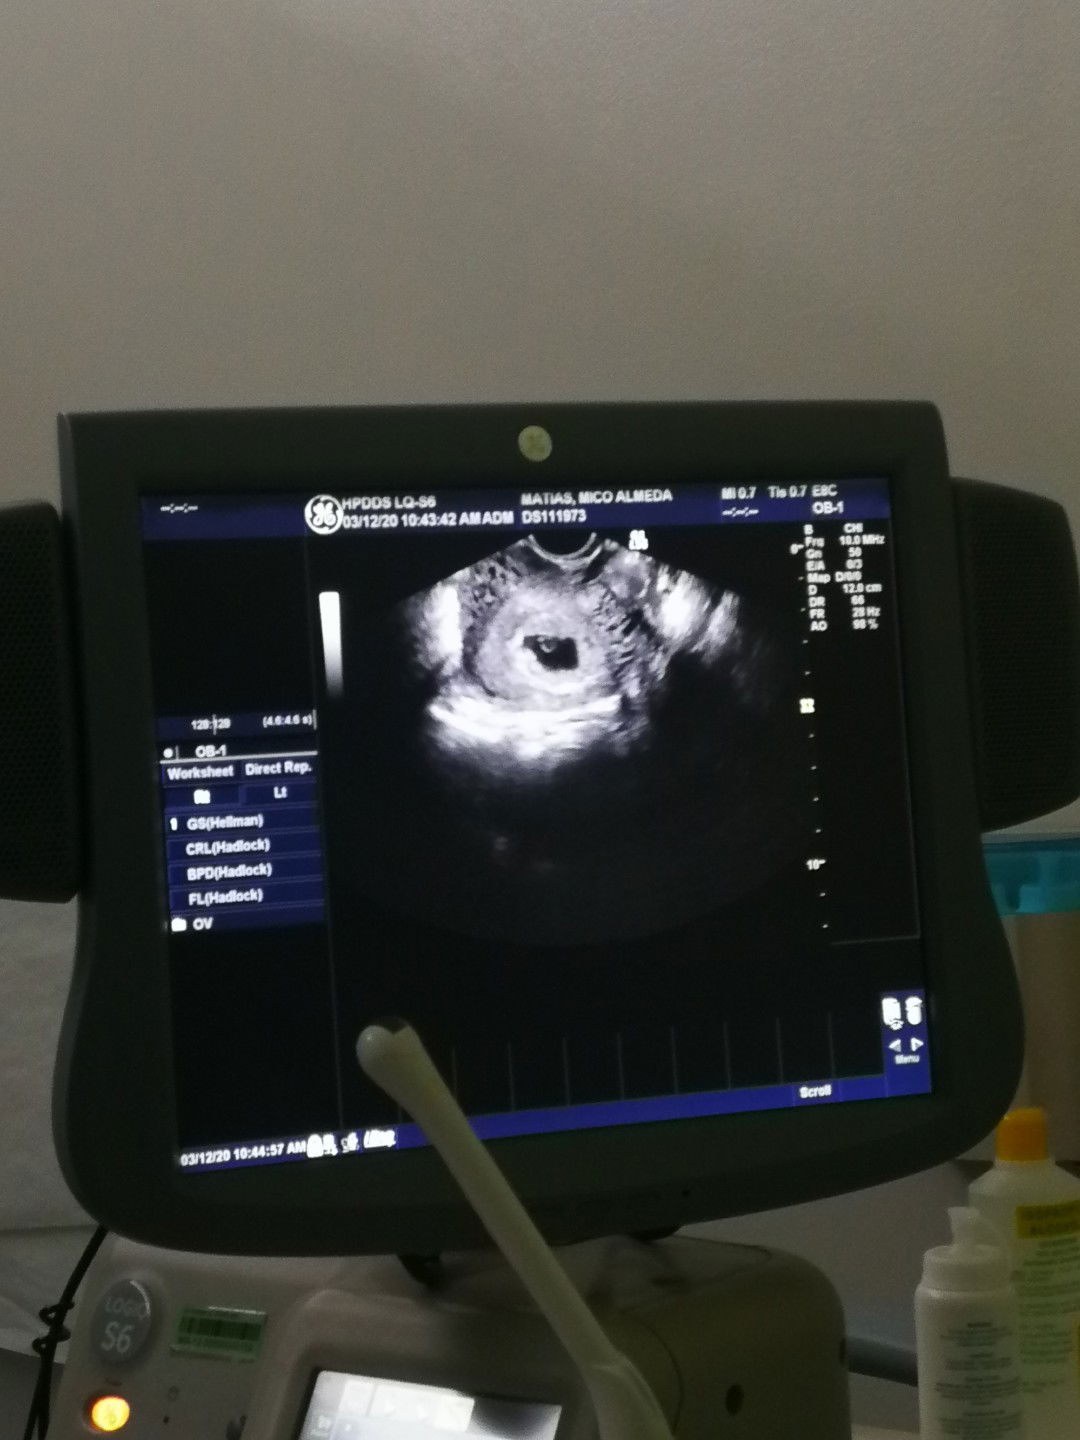

Few weeks nag post ako about dito.. Then iba iba yung comments.. Some posterior placenta is baby girl and some anterior placenta is baby boy.. So i asked my obegyne ☺️ "Dra. Question po? May kinalaman ba ang placenta kung posterior or anterior sa gender? Kasi po nag Google ako about sa pasts ultrasounds ko. Most of them showed Posterior, and my baby is boy.. Then i go to google to seek for meaning.. Sabi ni google most of posterior daw eh boy nga, is it true? " Then my reliable obegyne answered.. " No, definitely No.. Walang kinalaman sa posterior and anterior placenta kung ano ang magiging gender ni baby.. Kumbaga ganito yan.. Ang placenta ay parang ugat ng halaman.. Kung saan siya tumubo doon siya kakapit.. Hindi pwedeng pag basihan ang anterior o posterior placenta para sa gender ni baby.. Mostly pwedeng tama yung na basa mo sa google pero hindi yan proven lalo pag ultrasound na.. Meron talagang posterior na baby girl at anterior na baby boy.. Kaya natin na sasabi na ang bawat pag bubuntis ay iba iba walang nagkaka pareho.. " Kaya na linawan na ko☺️ ayun pala yun mga mommies.. Malinaw na sakin yung sagot.. Iisa lang naman ang hiling nating lahat.. Makaraos ng matiwasay at magkaroon ng malusog at normal na anak❤️ Lip ko nga pala na walang absent sa pag sama tuwing check up and lab tests ko🥰#theasianparentph #pregnancy #sharingiscaring